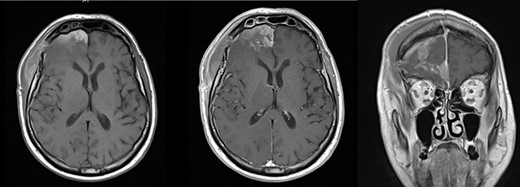

Initial assessment in the emergency room revealed a Glasgow Coma Scale (GCS) score of 11/15 (E1 V4 M6), equal and reactive pupils and a dense left hemiparesis—Medical Research Council Grade 1/5 power in both upper and lower limbs. His presenting blood pressure was 162/109 mmHg. He had been taking aspirin with prophylactic indication. Initial non-contrast computed tomography (CT) scan of the brain revealed a massive right frontal intracerebral hematoma with significant vasogenic edema and mass effect as shown in Figure 1.

CT brain scan showing massive right frontal ICH causing significant mass effect and transtentorial herniation (superior left and inferior right). There is also moderate vasogenic edema (superior and inferior left). The mass extends to the floor of the anterior cranial fossa (superior right and inferior left).